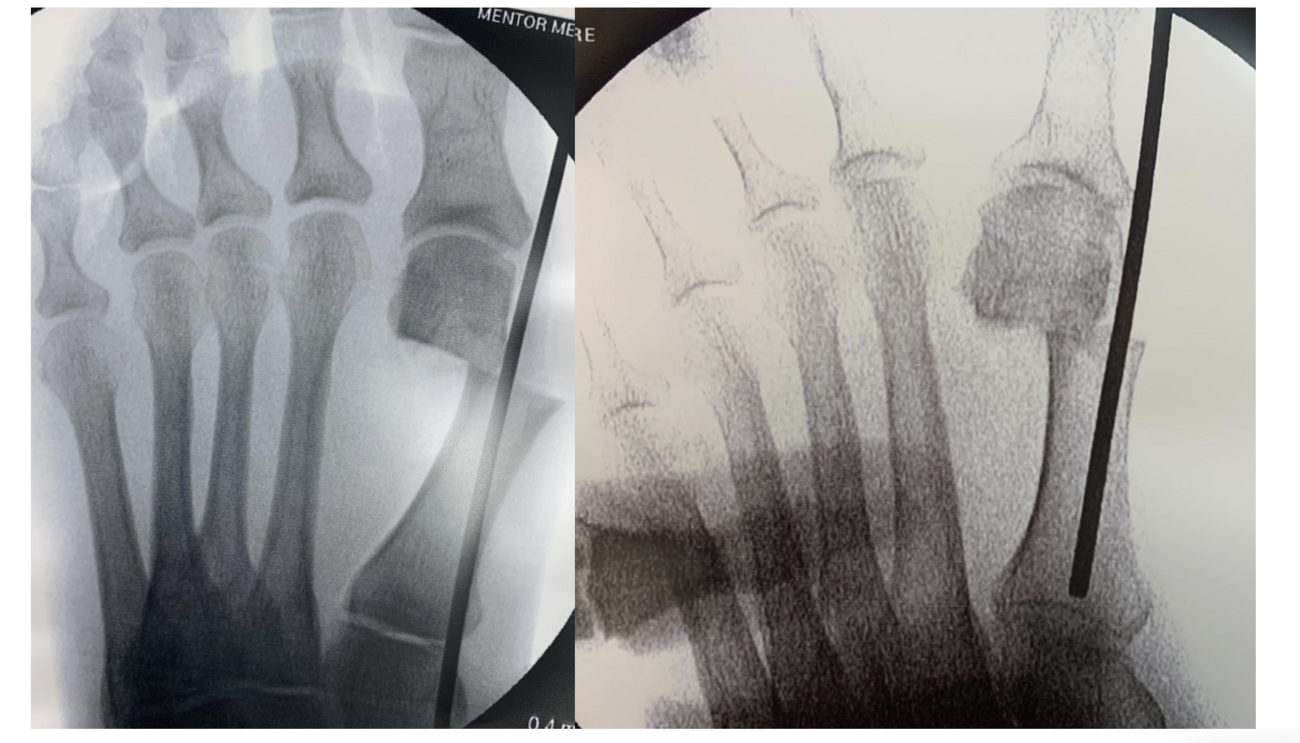

Metatarsal Head Translation. First, shift the metatarsal head laterally by inserting an elevator or hemostat (see third photo above) into the medullary canal. Maintaining the elevator or hemostat parallel to the long axis of the first metatarsal during the shift will prevent deviation of the capital fragment in the sagittal plane.

Next, the surgeon should rotate the hallux in a varus position to correct the frontal plane deformity (see fourth photo above). Once the metatarsal head is translated and the frontal plane is reduced, one can hold the reduction with the non-dominant hand. A large K-wire or Steinmann pin should capture the medial capsular tissue at the hallux and metatarsal head. This step can be performed prior to obtaining reduction of the metatarsal head to allow for easier placement into the metatarsal shaft. Following reduction, the surgeon will advance this wire intramedullary to the metatarsal base or across the first TMTJ for additional stability (see fifth photo above). Another method to maintain correction is to provisionally fixate the first metatarsal head to the second with a K-wire, with the intermetatarsal angle and tibial sesamoid position corrected. Consider lateral capsular or fibular sesamoid release if reduction is difficult. Also, consider an MIS Akin if the hallux remains in valgus or when there is an intrinsic deformity to the digit.

Wire Placement For Percutaneous Screw Fixation. Surgeons may place wires in the first metatarsal before the osteotomy, from the medial aspect of the first metatarsal up to the lateral cortex. Following osteotomy of the metatarsal, the surgeon can then shift the metatarsal head and advance the wires to capture the fragment. This will prevent loss of reduction after manipulation. The proximal wire should be just distal to the first tarsometatarsal joint, while the distal wire should be approximately two cm proximal to the osteotomy site. The distal wire does not need to purchase the lateral cortex of the first metatarsal. The proximal wire must purchase the lateral cortex of the first metatarsal and may exit bone before re-entering the metatarsal head. Be cognizant of maximum screw length to help in planning of wire trajectory (see eighth photo above).